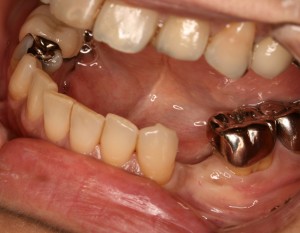

左下6 : オールセラミッククラウン

左下7 : 銀歯(保険適応)

左上5 : オールセラミッククラウン

左上6 : ハイブリットクラウン